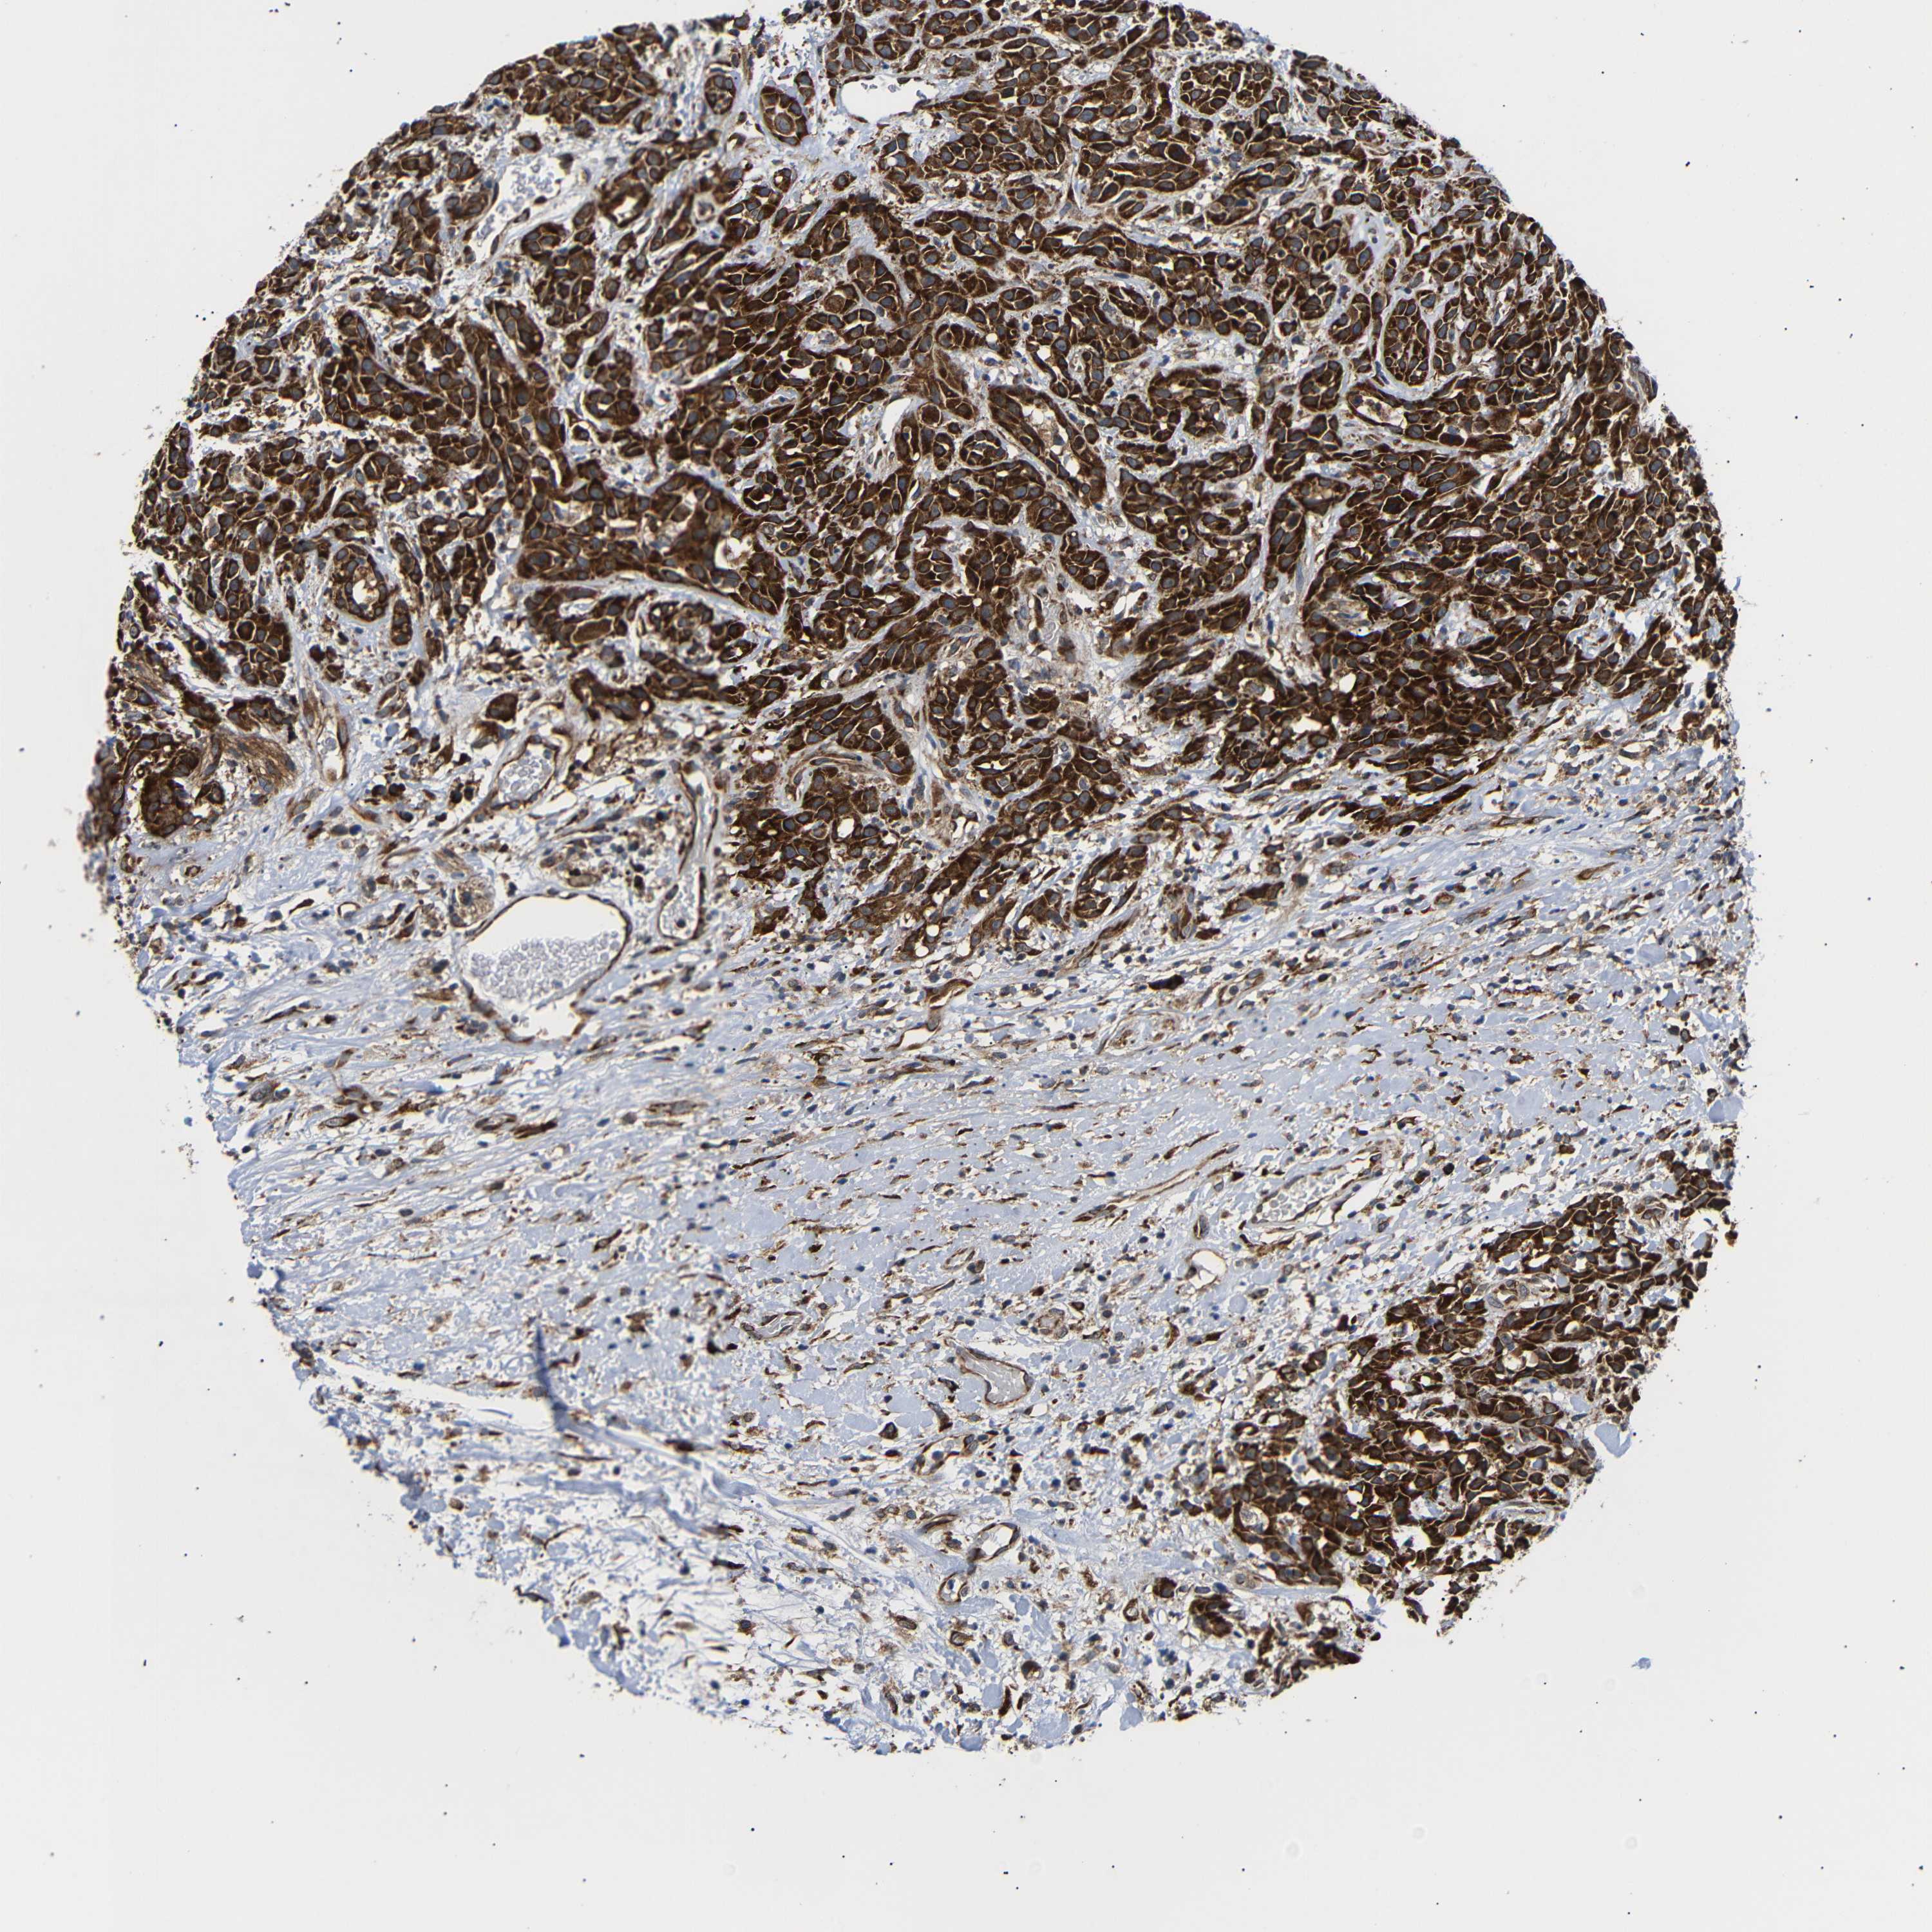

HEAD AND NECK CANCER - Protein expressioni

A mouse-over function shows sample information and annotation data. Click on an image to view it in a full screen mode. Samples can be filtered based on level of antibody staining by selecting one or several of the following categories: high, medium, low and not detected. The assay and annotation is described here.

Antibody stainingi

Antibody staining in the annotated cell types in the current human tissue is reported as not detected, low, medium, or high, based on conventional immunohistochemistry profiling in selected tissues. This score is based on the combination of the staining intensity and fraction of stained cells.

Each image is clickable and will lead to virtual microscopy that enables deeper exploration of all samples and also displays staining intensity scores, fraction scores and subcellular localization as well as patient and tissue information for each sample.

Antibody HPA014030

Staining

High

Medium

Low

Not detected

Intensity

Strong

Moderate

Weak

Negative

Quantity

>75%

75%-25%

<25%

None

Location

Nuclear

Cytoplasmic/membranous

Cytoplasmic/membranous,nuclear

Adenocarcinoma, NOS